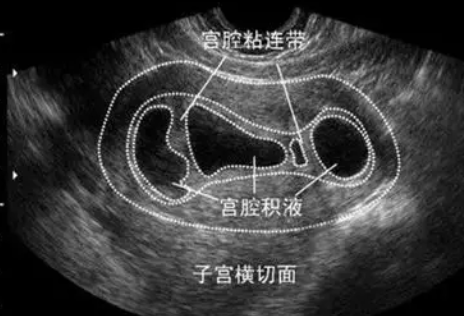

子宮內(nèi)膜在陰道超聲下內(nèi)膜相關(guān)參數(shù)的改變

IUA主要表現(xiàn)為:

子宮內(nèi)膜厚度單層<3mm;

內(nèi)膜薄厚不均,局部不連續(xù);

內(nèi)膜回聲增強,呈粗線狀;

宮腔線不清等。